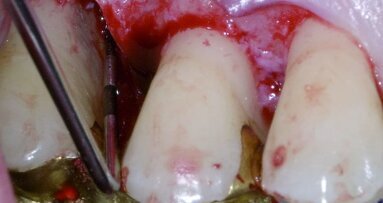

Das Webinar präsentiert einen systematischen Überblick über Prävention und Behandlung bzw. Management von Parodontalerkrankungen anhand eines einfachen, Vier-Schritte-Plans. Zu den Themen gehören die Integration des Patienten in den Behandlungsprozess durch eine kontinuierliche Motivation, Optionen für ein optimales Debridement und eine effektive Initialtherapie, moderne Techniken für Regeneration und Reattachment sowie ein sicheres und nichtabrasives Management von Belägen bzw. Biofilmen. Die Referentin spricht außerdem über ihre Erfahrung mit den neuesten Instrumenten und Lösungen für die Karieserkennung, Zahnbelagsentfernung, -reinigung und -politur.

ST. PÖLTEN – Die Parodontaltherapie fasst alle Methoden zusammen, mit dem Ziel der Neubildung der verloren gegangenen Strukturen des ...